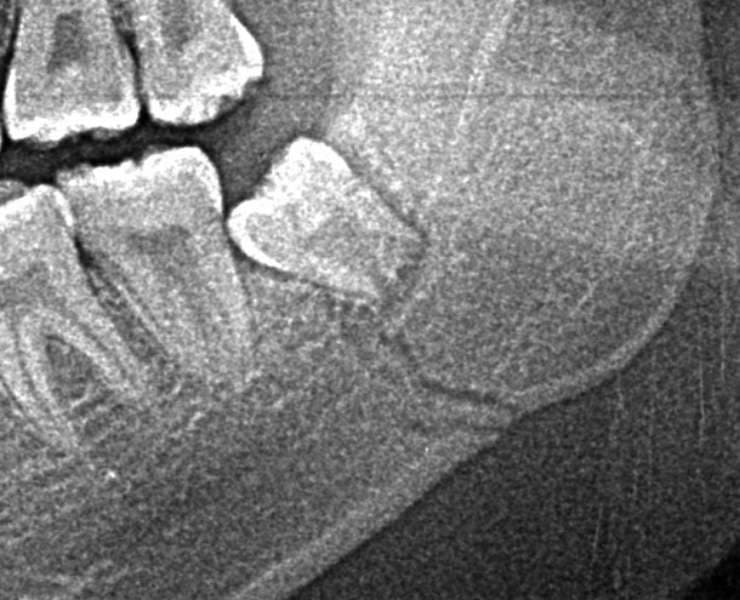

顎の骨折に親知らずが関係している症例

親知らずが原因で、顎の骨が薄くなり、骨折しています。

親知らずに沿って入っている黒い線(骨折線)が確認できます。